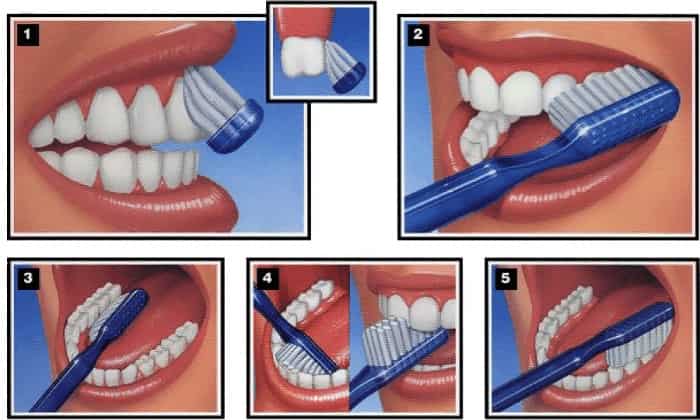

دهان و دندان